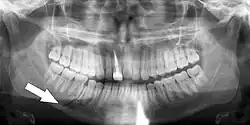

Essa lesão envolve o osso alveolar e pode se estender além do alvéolo. [7] [8] Existem 5 tipos diferentes de fraturas alveolares:

- Fratura comunicada da parede do alvéolo

- Fratura da parede da cavidade

- Fratura dento-alveolar (segmentar)

- Fratura da maxila: Fratura Le Fort, fratura zigomática, erupção orbital

- Fratura da mandíbula

As lesões traumáticas envolvendo os alvéolos podem ser complicadas, pois não ocorrem de forma isolada, muitas vezes se apresentando juntamente com outros tipos de lesões do tecido dentário.

Sinais de fratura dento-alveolar:

- Elementos dentários movendo-se juntos como um segmento e normalmente são deslocados.

- Hematomas na gengiva inserida.

- Gengiva em toda a linha de fratura frequentemente lacerada[9].

Investigação: Requer mais de uma visualização radiográfica para identificar a linha de fratura.

Tratamento: Reposicionar os dentes deslocados sob anestesia local e estabilizar o segmento móvel com uma tala por quatro semanas; suturar quaisquer lacerações de partes moles.